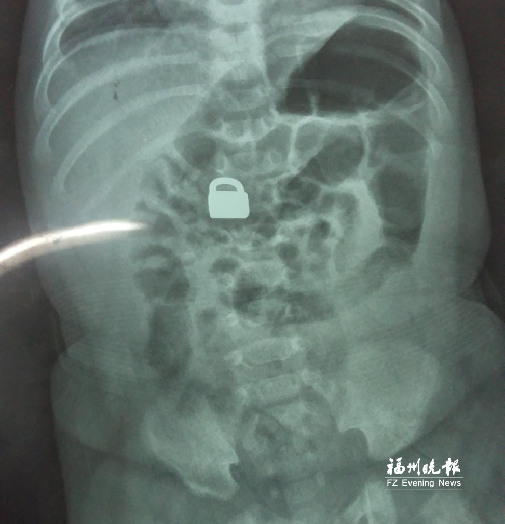

7.25龍巖當?shù)蒯t(yī)院拍的X光片顯示,平安鎖在寶寶體內(nèi)。

這名60天大的“神奇寶寶”來自龍巖,哥哥也只有兩歲。7月25日,兄弟倆的媽媽突然發(fā)現(xiàn)寶寶胸前掛著的平安鎖不見了,便問小哥哥是否看到弟弟的平安鎖。小哥哥回答,他把平安鎖塞到弟弟嘴里了。媽媽趕緊檢查寶寶嘴巴,沒有發(fā)現(xiàn)平安鎖。雖然寶寶沒有任何癥狀,但媽媽還是帶著他去當?shù)蒯t(yī)院檢查。拍片結(jié)果顯示,平安鎖真的在寶寶體內(nèi)。

“X光片顯示,那是一把1.5厘米×0.9厘米的平安鎖,有指甲蓋大小,已經(jīng)到了寶寶的小腸處?!?月28日,陳惠萍見到寶寶時,吃了一驚,“他真的好小,被抱在媽媽懷里,眼睛微微睜開,我估計他的世界還是混沌的,沒想到就已經(jīng)接受了這么大的挑戰(zhàn)?!?/p>